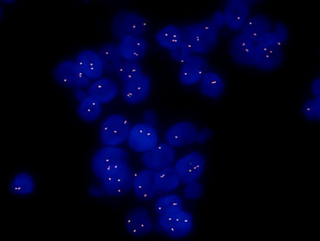

MF43-N+MSX11拍摄的FISH图片

FISH样品在紫外激发光的照射在,显现出蓝色的细胞轮廓的信号,在蓝色激发光的照射下在细胞内显现出绿色的探针信号,在绿色激发光的照射下在细胞内显现出红色的探针信号。